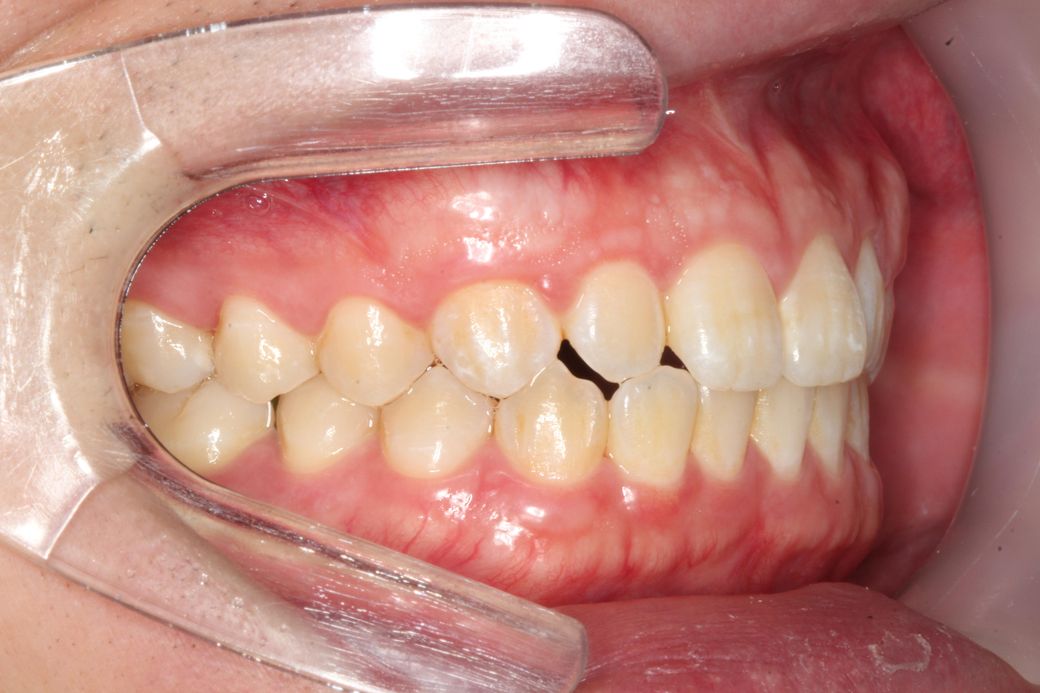

사진상 왼쪽어금니들은 윗아래 옆면 딱붙는 느낌이면

오른쪽은 옆면이 공간이 남는 느낌? 입니다

• 4번 째 사진

현재 교합이 완전하다고 할 수는 없습니다. 따라서 교정적인 힘으로 치열을 바꿀 수는 있어 보여도 상당히 어려운 과정을 거쳐야할 것으로 보이며 교정 전 후가 크게 달라지지 않을 수 있어 보입니다. 발치 교정도 현재로서는 애매하고 비발치 교정에도 한계가 있어 보입니다. 즉 정상범주에서 특별히 많이 벗어나는 것이 아니라는 것입니다.

이상적인 교합이면 가장좋겠지만, 작성자님의 상태의 교합이 크게 문제가 되어 보이진 않습니다. 다만, 기능적으로 문제가 있다면 교정을 고려해보셔도 되지만, 기능상으로 크게 문제가 없다면 그냥 지내셔도 상관없을것같습니다.